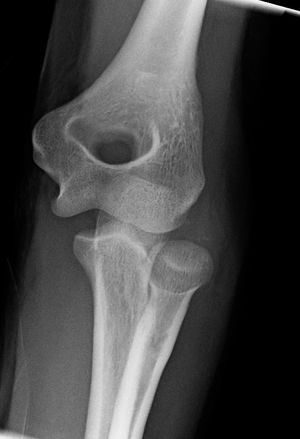

4. 발생

팔꿈치는 유아기 및 청소년기에 걸쳐 뼈가 만들어지는 중심(골화 중심)의 역동적인 발달을 겪는다. 방사선 사진에서 소아 팔꿈치를 평가할 때 골단 성장 중심의 출현 및 유합 순서가 외상성 골절이나 골단 분리를 정상적인 발달과 구별하는 데 매우 중요하다.[16] 출현 순서는 CRITOE라는 약어로 이해할 수 있는데, 이는 다음 뼈들이 나타나는 순서를 의미한다.

| 약어 | 뼈의 이름 | 나타나는 시기(세) |

| C | 자뼈머리 | 1 |

| R | 요골두 | 3 |

| I | 내측 상과 | 5 |

| T | 도르래 | 7 |

| O | 주두 | 9 |

| E | 외측 상과 | 11 |

이러한 골단 중심은 청소년기에 융합되며, 내측 상과와 주두가 마지막으로 융합된다. 융합 연령은 골화보다 더 가변적이지만, 일반적으로 각각 13, 15, 17, 13, 16, 13세에 발생한다.[16] 또한, 지방 패드 징후의 존재로 관절 삼출액의 존재를 추론할 수 있는데, 이는 일반적으로 생리학적으로 존재하지만, 액체에 의해 상승될 때는 병리학적이며, 뒤쪽에 있을 때는 항상 병리학적인 구조이다.[17]